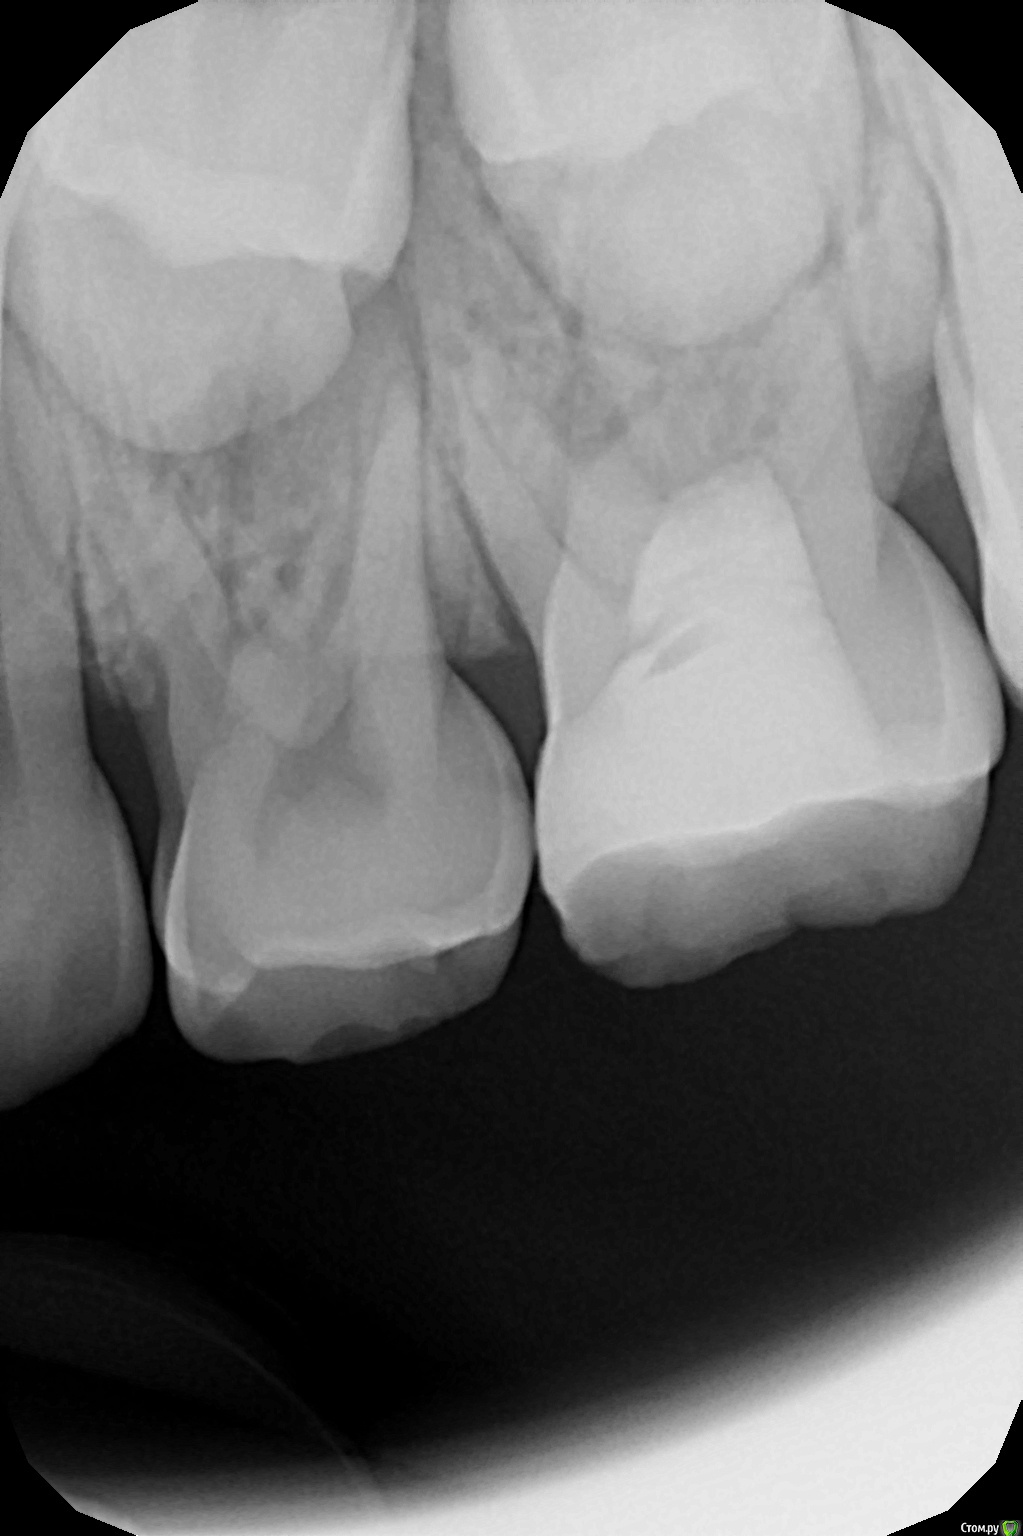

crown Опубликовано 19 октября, 2016 Автор Поделиться Опубликовано 19 октября, 2016 8 лет 2 месяца назад лечил 6.5 пульпитный с триоксидентом, сегодня отек в районе четверки и перкуссия ее болезненна, но она интактная. Решил полезть в 6.5, мб2 и мб1 прошел, закинул кальций, в небный не могу войти орет, дистальный вообще туго, облитерировалось по ходу все к чертям, пока оставил так. Но меня терзают сомнения, так как симптоматика вся на четвертом зубе и на снимке изменения в 6.4. Мамаша еще мозг выносит, сыпит вопросами как из пушки и тут не понятно то ли ребенка лечить то ли ей на вопросы отвечать. Ссылка на комментарий

Mikhail_29_rus Опубликовано 23 октября, 2016 Поделиться Опубликовано 23 октября, 2016 8 лет 2 месяца назад лечил 6.5 пульпитный с триоксидентом, сегодня отек в районе четверки и перкуссия ее болезненна, но она интактная. Решил полезть в 6.5, мб2 и мб1 прошел, закинул кальций, в небный не могу войти орет, дистальный вообще туго, облитерировалось по ходу все к чертям, пока оставил так. Но меня терзают сомнения, так как симптоматика вся на четвертом зубе и на снимке изменения в 6.4. Мамаша еще мозг выносит, сыпит вопросами как из пушки и тут не понятно то ли ребенка лечить то ли ей на вопросы отвечать.У меня тоже бывали подобные случаи, но как правило, зуб выстреливал сразу после лечения. Но тогда я "грешил " с гемостазом. На 65 зубе правило "3 минут" сработало? Гемостазу не помогали ? Если все с 65 сделали верно , то скорее всего 64. В любом случае, удачи в решении не самой простой задачи в особенности с непростой мамой Ссылка на комментарий

crown Опубликовано 23 октября, 2016 Автор Поделиться Опубликовано 23 октября, 2016 На счет гемостаза не помню. Мож терпел малец и не жаловался, пока щека не припухла. Спасибо Михаил. Ссылка на комментарий

Olga25 Опубликовано 14 ноября, 2016 Поделиться Опубликовано 14 ноября, 2016 Лично я бы удалила. там же очаг деструкции по бифуркации. прогноз для зуба неблагоприятный да еще и зачатком рискуете. жаль, что я еще не совсем разобралась да и с техникой не очень дружу. а так бы показала снимок на котором видно полную резорбцию корня зачатка постоянного 14 зуба после эндолечения 54 зуба. вернее на зачатке были видны следы пломбировочной массы, 54 зуб удалился, зачаток 14 прорезался, но корень рассосался. так и болтается шляпка коронки постоянного зубаЗдравствуйте!Я понимаю,что из-за проблем с мол.зубом может произойти и гибель зачатка,но при тяжел.осложнениях.В данном случае возможна гипоплазия. Почему корень постоянного зуба рассосался?Я таких случае не встречала.Какой прогноз для такого пост. зуба?? Ссылка на комментарий

Kota Опубликовано 15 ноября, 2016 Поделиться Опубликовано 15 ноября, 2016 Лично я бы удалила. там же очаг деструкции по бифуркации. прогноз для зуба неблагоприятный да еще и зачатком рискуете. жаль, что я еще не совсем разобралась да и с техникой не очень дружу. а так бы показала снимок на котором видно полную резорбцию корня зачатка постоянного 14 зуба после эндолечения 54 зуба. вернее на зачатке были видны следы пломбировочной массы, 54 зуб удалился, зачаток 14 прорезался, но корень рассосался. так и болтается шляпка коронки постоянного зубаЗдравствуйте!Я понимаю,что из-за проблем с мол.зубом может произойти и гибель зачатка,но при тяжел.осложнениях.В данном случае возможна гипоплазия. Почему корень постоянного зуба рассосался?Я таких случае не встречала.Какой прогноз для такого пост. зубпочему рассосался я не знаю. эндодонтическое лечение 54 зуба проводилось не у нас. если не забуду, то постараюсь выложить фото. Ссылка на комментарий